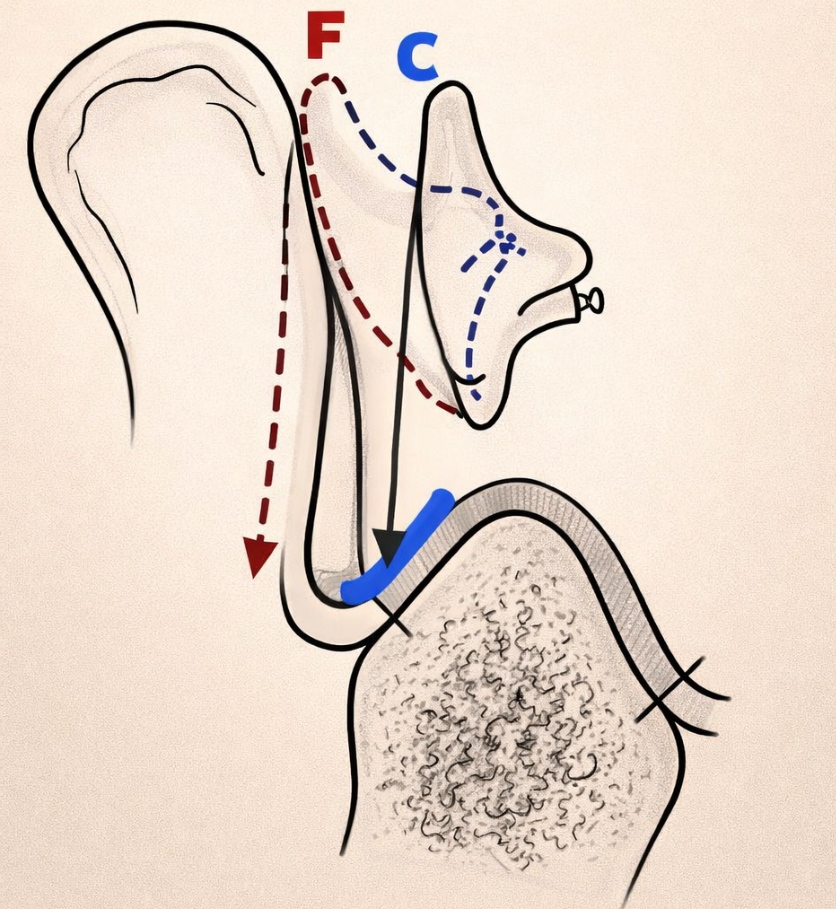

- Les dents antéro-inférieures devront être montées dans l’aire de sustentation d’Ackermann (l’espace délimité par le sommet de la crête antérieure et de son versant vestibulaire).

Sa position s’inscrit dans l’aire de sustentation d’Ackermann. Elle est montée sur le versant externe de la crête (talon de la dent placé de 1 à 2 mm en avant de la crête).

Légère inclinaison linguo-vestibulaire de 10° qui ne doit pas aboutir à un contact avec la lèvre inférieure.

F= position erronée des incisives inférieures.